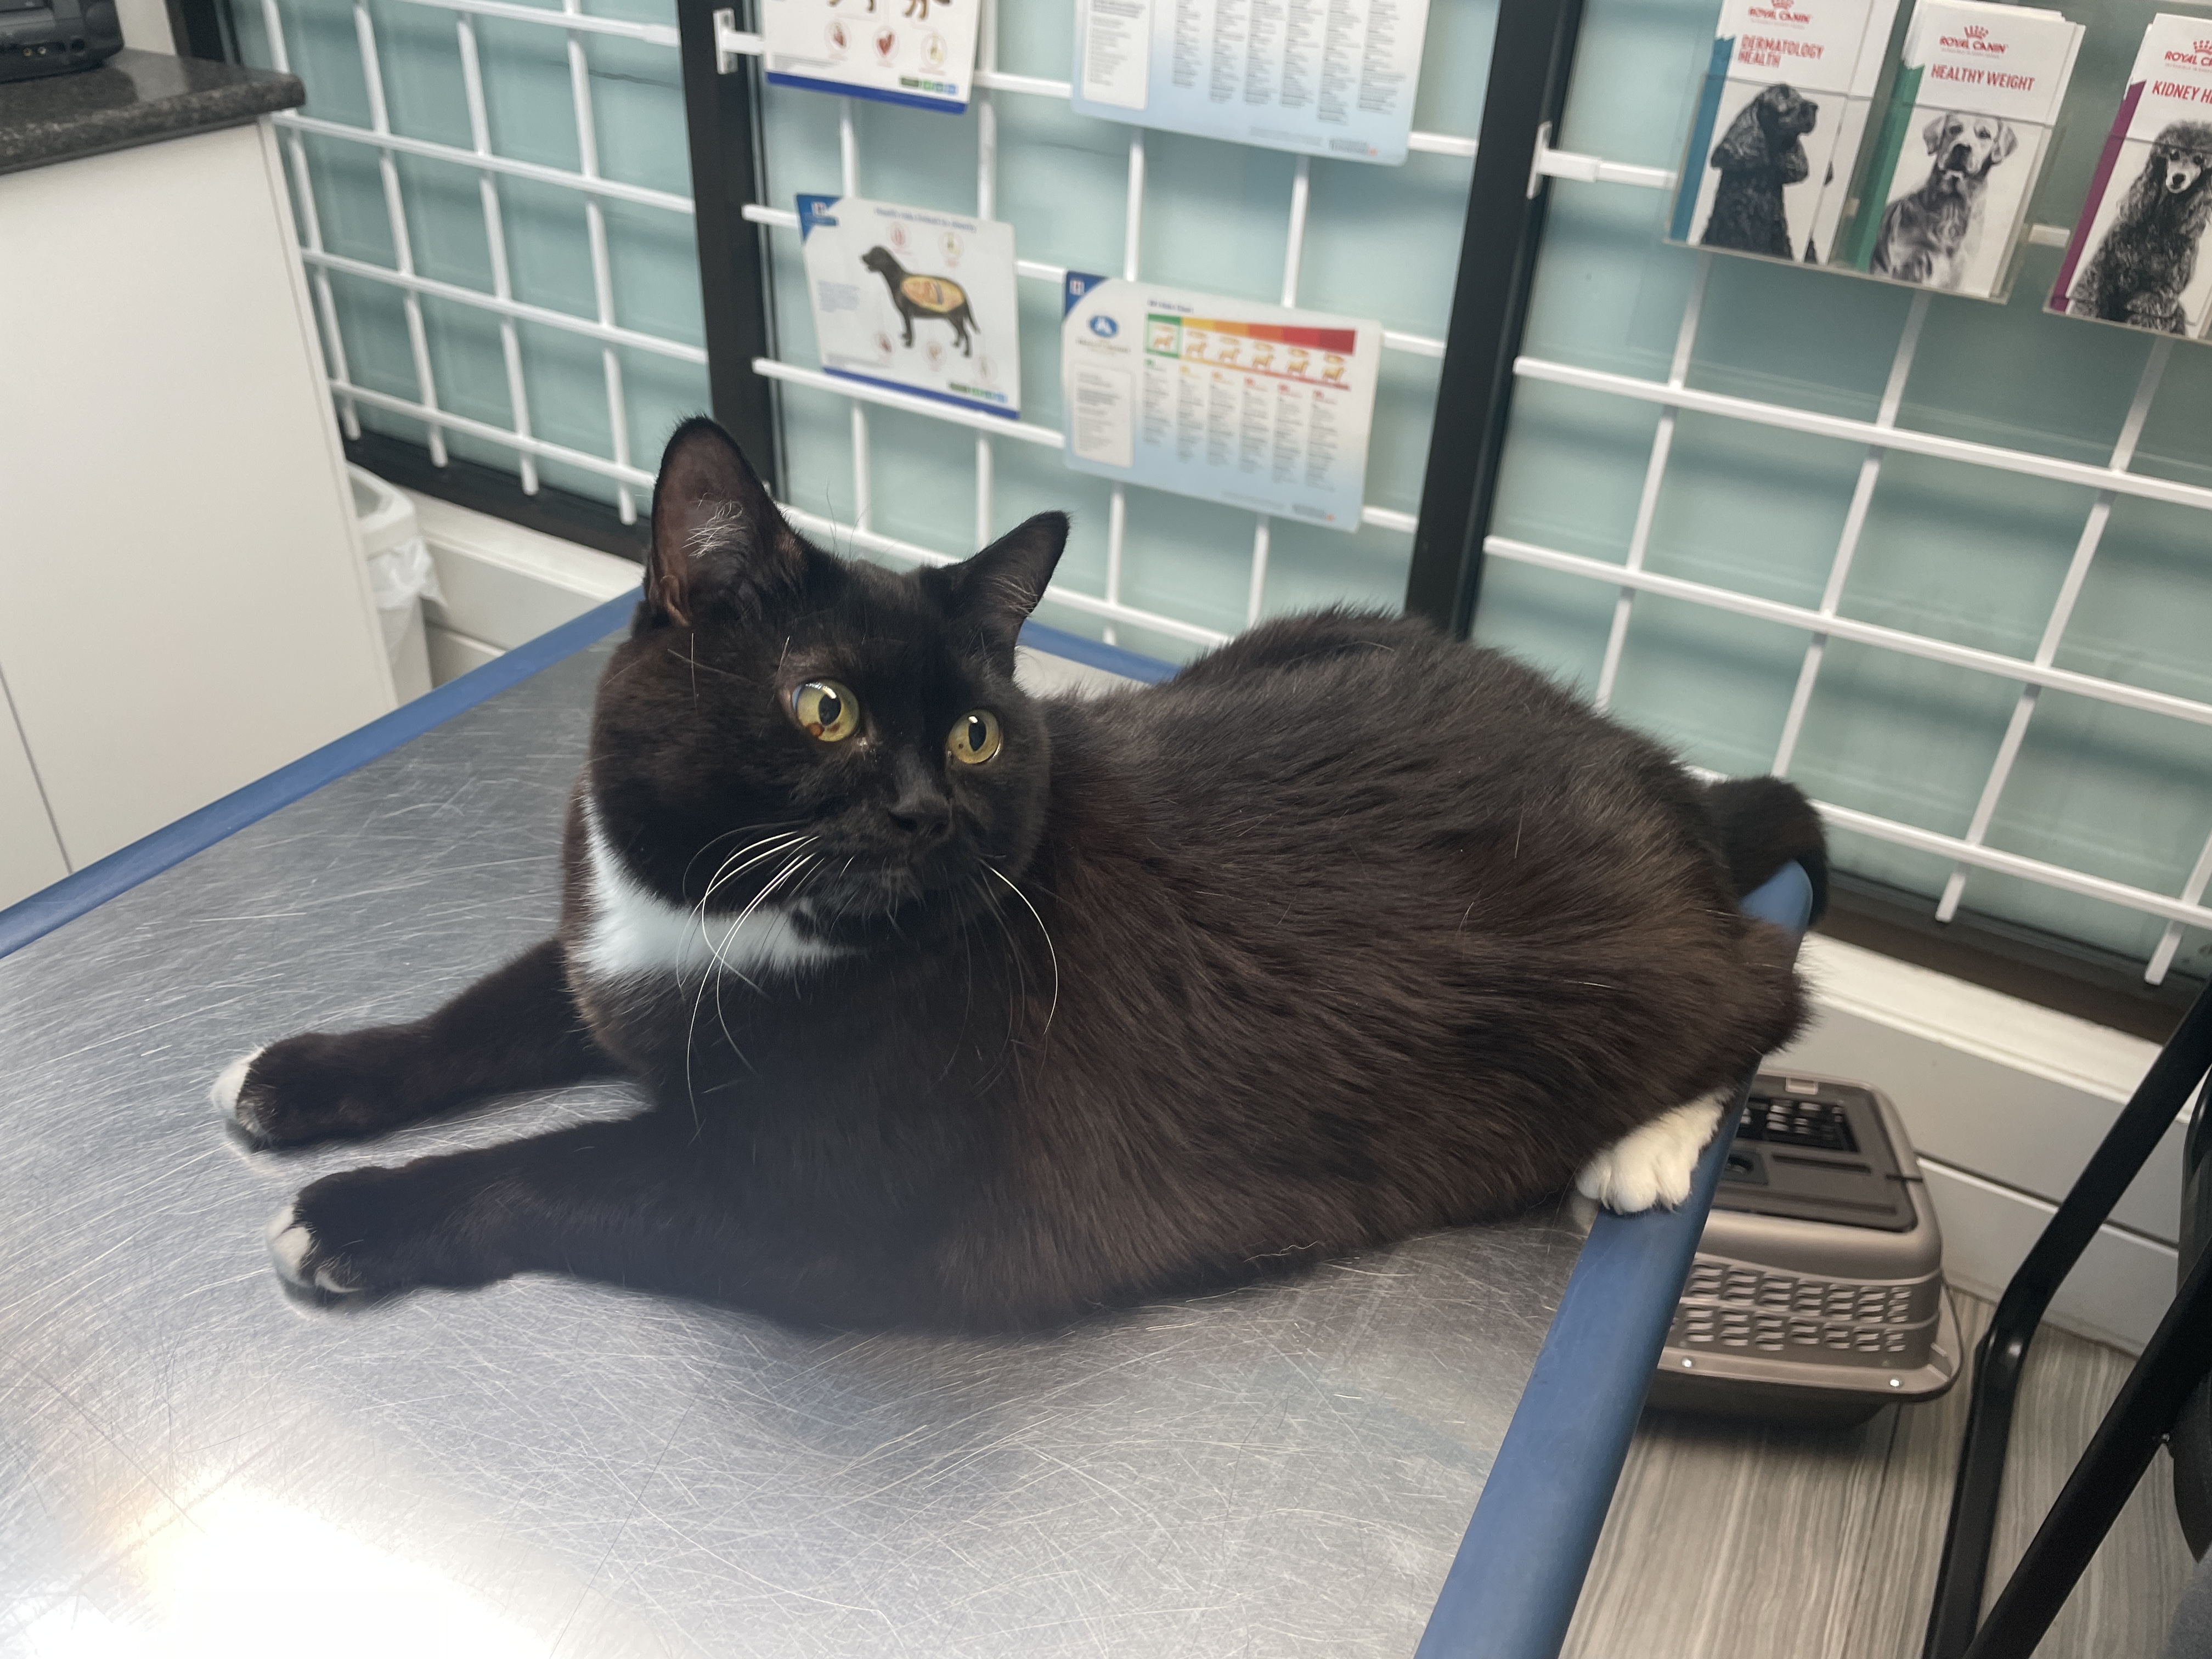

안녕하세요.

혹시라도 저희냥이와 비슷한 질병이나 증상이 있는 다른 냥이들에게

도움이 될까싶어 캐나다에사는 저희 냥이의 투병일지를 공유합니다.

저희냥이는 원래 어릴때부터도 토를 잘하던 아이긴 했어요.

울고불고 무서워하는 저희냥이 달래며 도착한 병원.